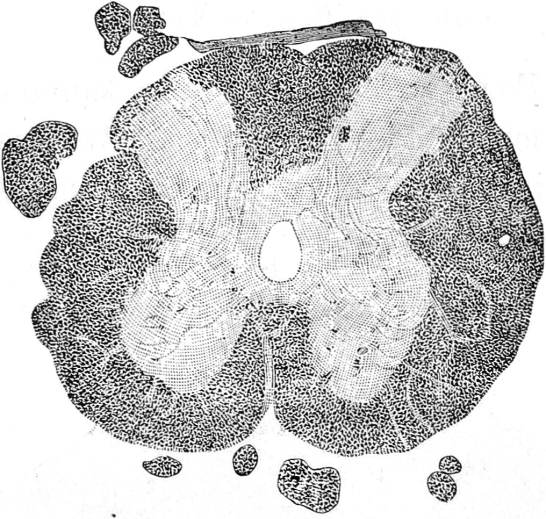

Въ поясничномъ утолщеніи спинного мозга авторомъ найдены слѣдующія патологическія измѣненія:

- перерожденіе переднихъ и заднихъ корешковыхъ волоконъ;

- перерожденіе тѣхъ по преимуществу волоконъ сѣраго вещества, которыя являются продолженіемъ корешковыхъ волоконъ;

- зернистое перерожденіе нервныхъ клѣтокъ въ обоихъ переднихъ рогахъ,

- рѣзкое перерожденіе обоихъ заднихъ столбовъ, но особенно праваго;

- незначительное диффузное перерожденіе обоихъ передне-боковыхъ столбовъ.

Въ другихъ отдѣлахъ спинного мозга констатировано авторомъ только восходящее перерожденіе праваго Голлева столба.

Нѣкоторыя изъ вышеприведенныхъ измѣненій спинного мозга авторъ ставитъ въ зависимость отъ омертвѣнія праваго сѣдалищнаго нерва, напр. перерожденіе переднихъ и заднихъ корешковыхъ волоконъ и перерожденіе праваго Голлева столба, и только перерожденіе клѣтокъ переднихъ роговъ и волоконъ передне-боковыхъ столбовъ онъ ставитъ въ зависимость отъ анэміи. Однако авторъ не отрицаетъ возможности и другого объясненія, хотя бы существованіемъ у больного нефрита.